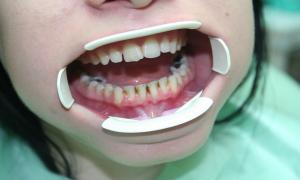

Chrup pred dentálnou hygienou, s viditeľnými povlakmi od čaju, kávy, cigariet

Chrup po dentálnej hygiene, všetky pigmenty a povlaky sú odstránené